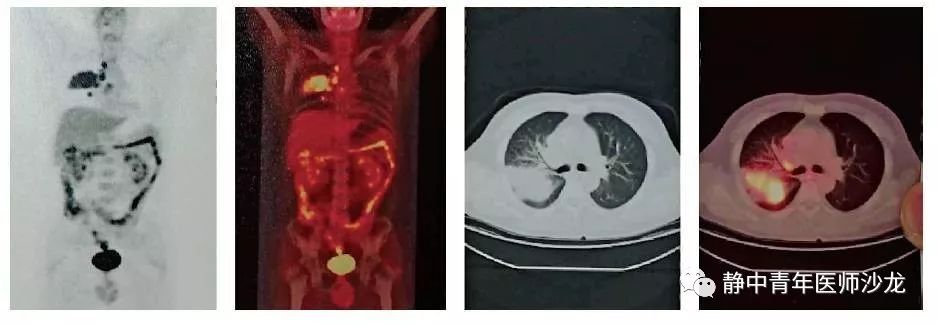

【病案分析】甲状腺癌肺转移:简单中的不

637x771 - 521KB - PNG